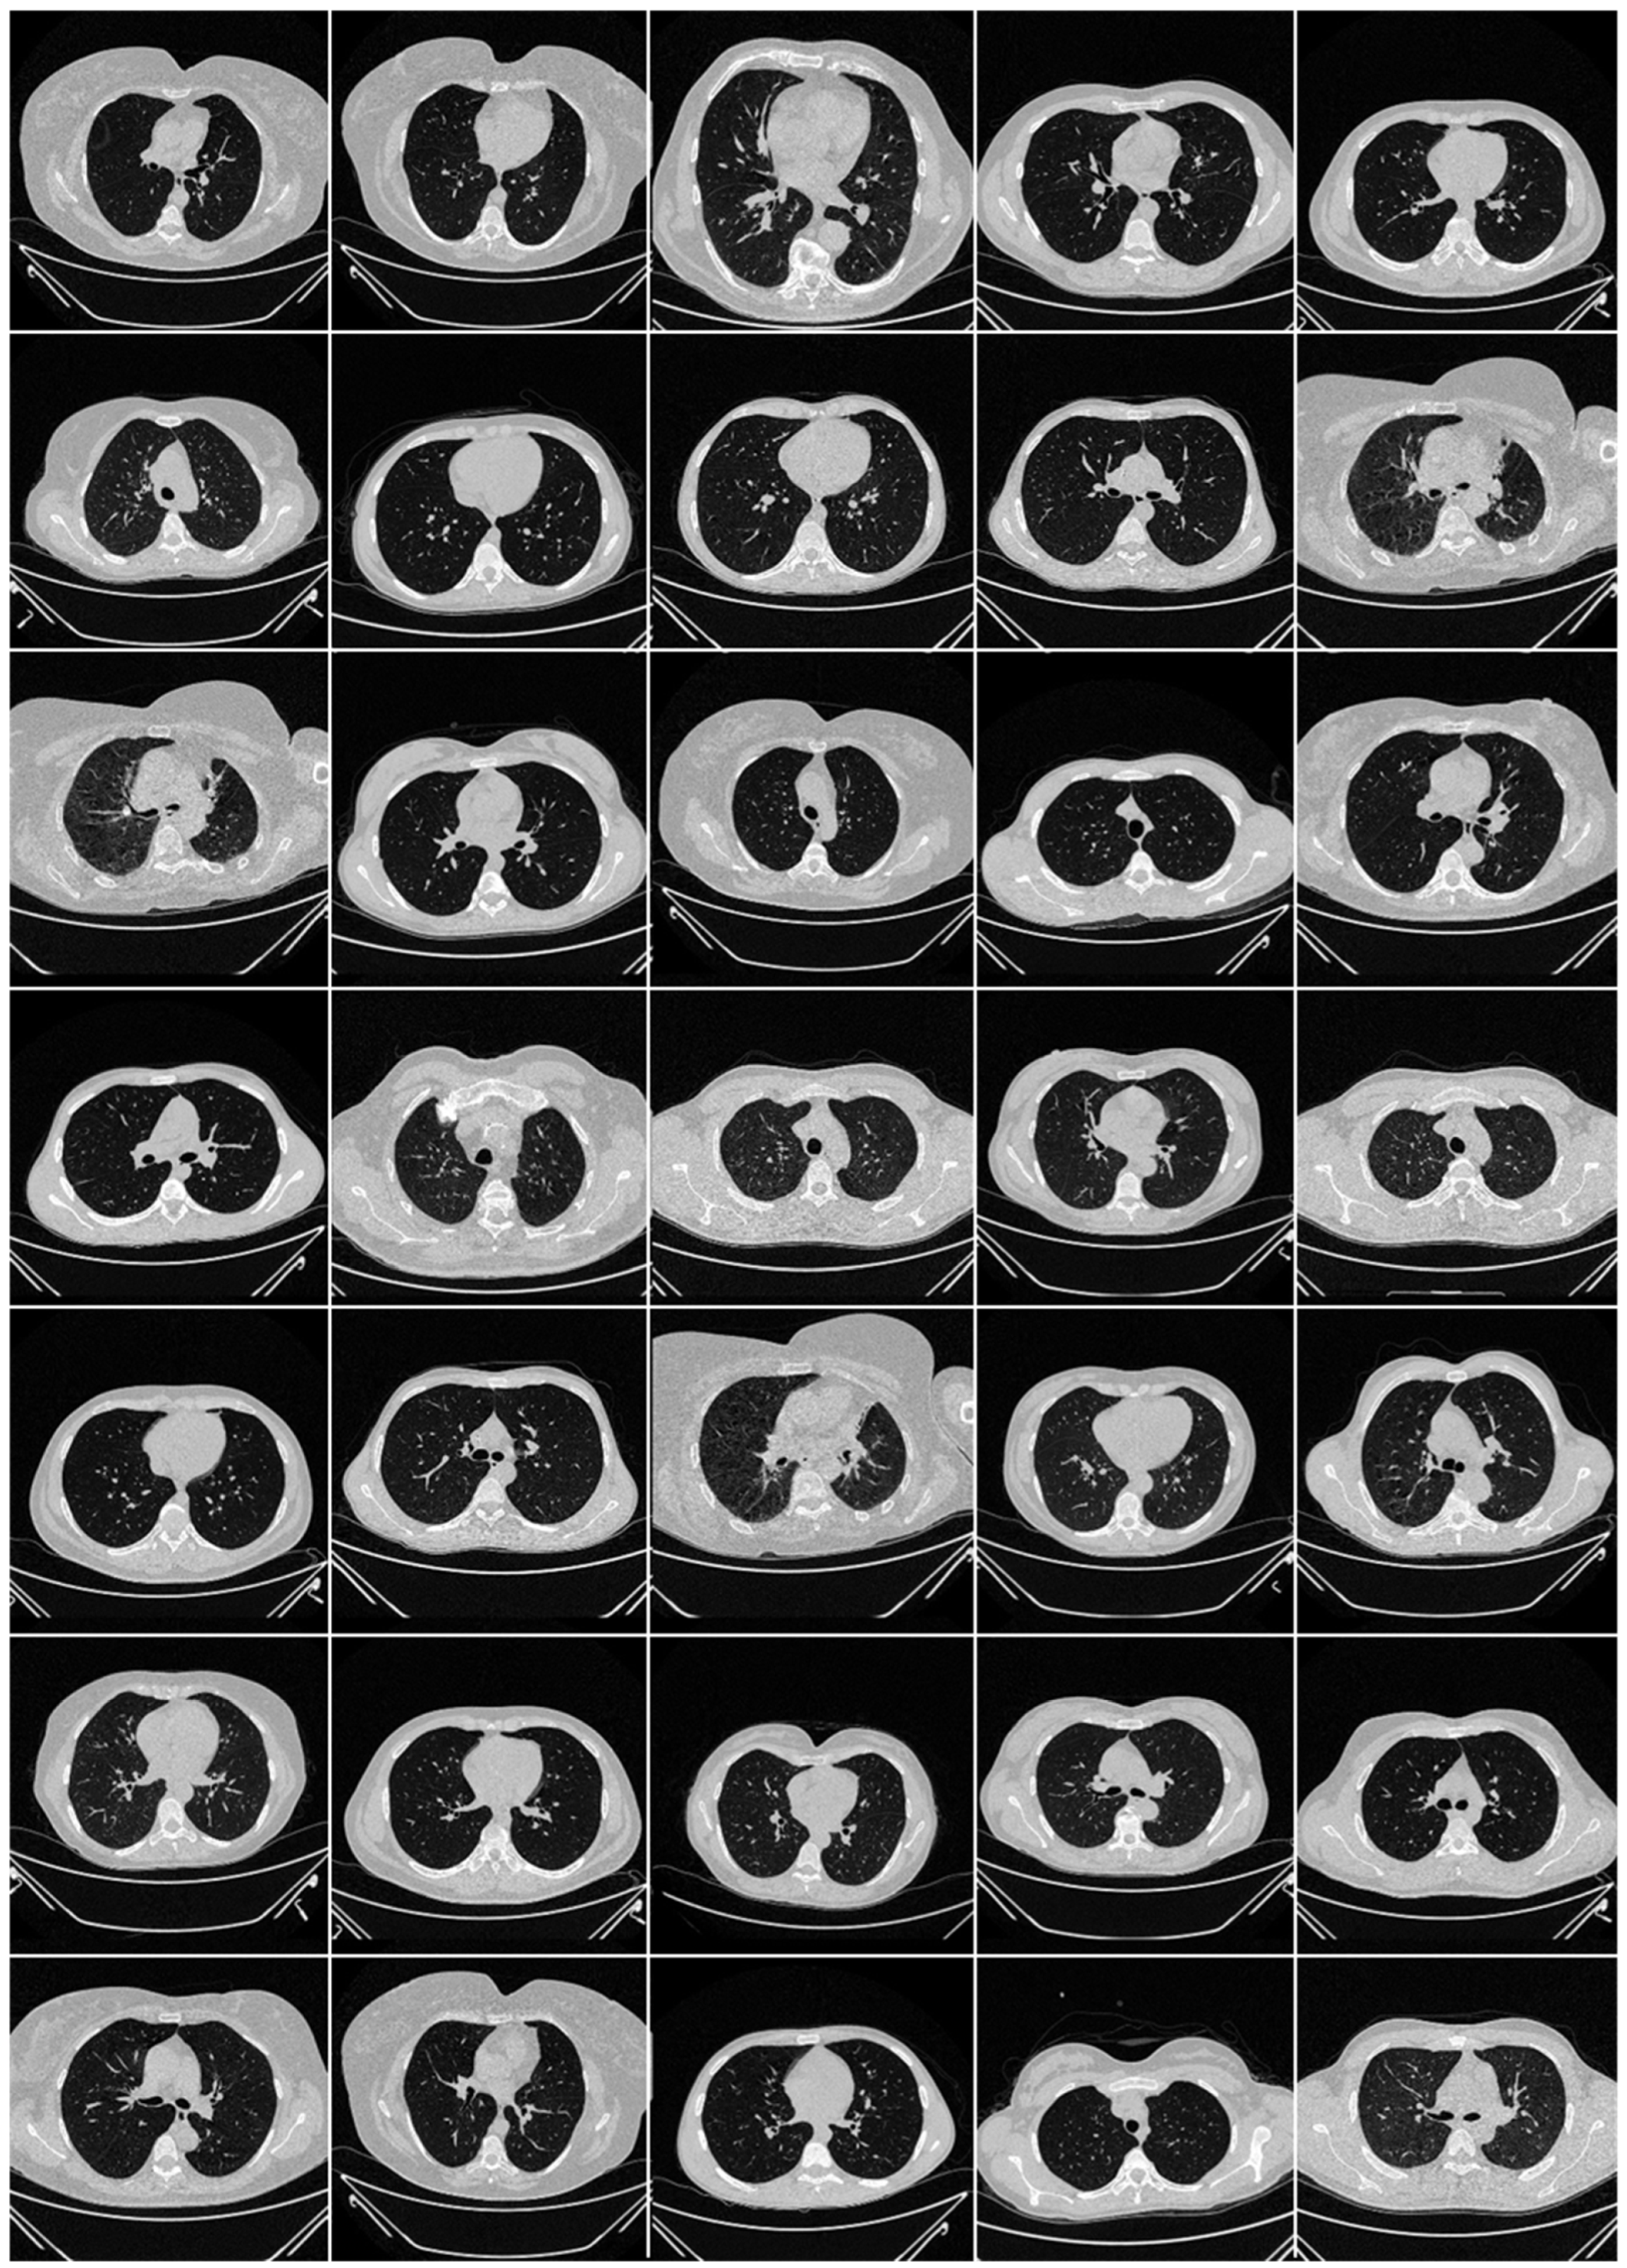

2.2. Image Acquisition and Data Preparation

2.2.1. Croatian Data Set

2.2.2. Italian Data Set